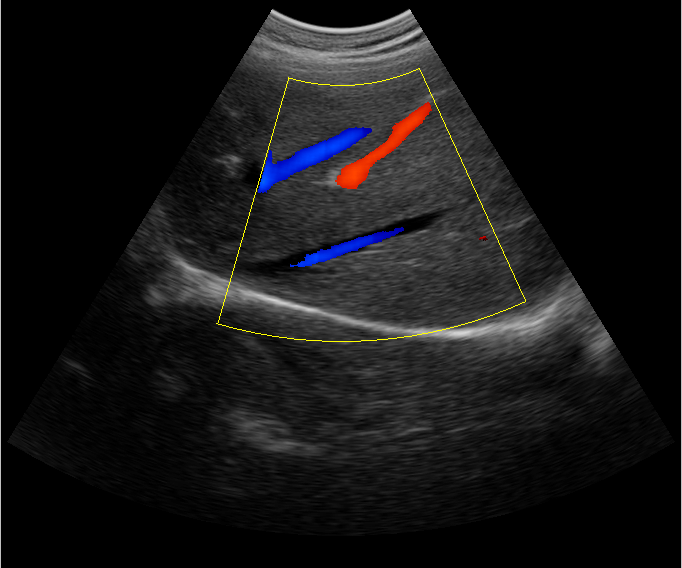

肝臟B超臨床圖

B超檢查主要是檢測肝臟的外形、大小、膽囊、門靜脈、回聲粗線等問題。由于乙肝病毒造成肝細胞破損嚴重,肝細胞出現問題,發生異常外形就會改變,通過B超檢查就能很清楚的檢查出肝臟受損的程度,以及肝臟的大小是否改變,肝臟是否發展為肝纖維化、肝硬化等。還可以檢查門靜脈主干內徑是否增寬等情況。

肝臟B超還可以通過肝臟的門靜脈、回聲粗線、膽囊等指標來診斷病情。由于肝炎病毒長期侵害會造成肝細胞破損嚴重,肝細胞出現異常,肝臟發生異常時外形就會改變。通過肝臟B超檢查就能很清楚地看出肝臟的受損程度,以及肝臟的大小、形態、回聲等是否正常。有利于肝臟的疾病的正確診斷。